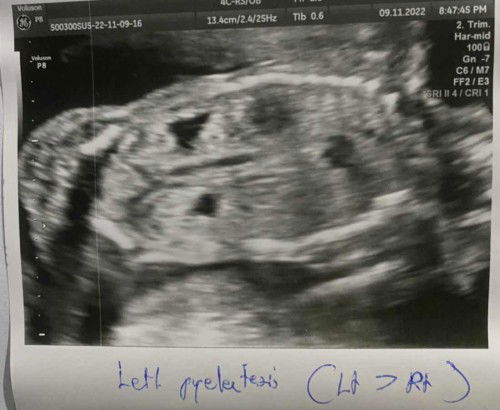

สอบถามค่ะแม่ๆ มีแม่คนไหนอัลตราซาวด์ดูอวัยวะภายในของน้อง แล้วพบว่าไตบวมน้ำบ้างมั้ยคะ ของแม่บ้านนี้เจาะเลือดตรวจดาวน์ซินโดรม ผลออกมาว่า เสี่ยงต่ำ แต่คุณหมออัลตราซาวด์แจ้งว่าน้องมีโอกาสเป็นดาวน์ซินโดรม เพราะไตบวมน้ำทั้งสองข้าง แต่ข้างซ้ายโตกว่าข้างขวา ขอความคิดเห็นแม่ๆที่มีประสบการณ์หรือแม่ๆบ้านไหนที่มีน้องเป็นดาวน์หน่อยค่ะ #อายุครรภ์ 20+6 วีค